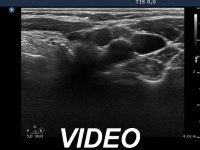

Ultrasonography: We could not find thyroid parenchyma. A small lymph node was present lateral to the left thyroid bed. The hilum was absent.